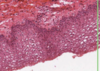

What type of epthielium is this?

Where is it found

Keratinised stratified squamous epithelium

- Epidermis

- Lower layers are similar to stratified squamous

- Upper layers synthesise a unique collection of proteins - interact with cytoskeleton of cell to produce keratin

- Keratin: a dense protein that fills the cytoplasms of cells = tough and waterproof

- When the cell is full of keratin they die and are sloughed off

Left = Hairless skin at lower lip

pink = dead keratinised squames

Boundary later with blue keratohyaline granules STRATUM GRANULOSUM